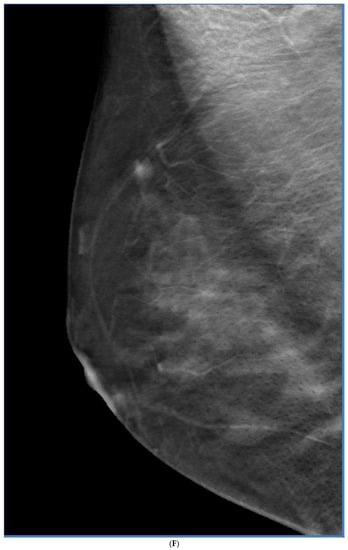

8. Contrast-Enhanced Mammography (CEM)